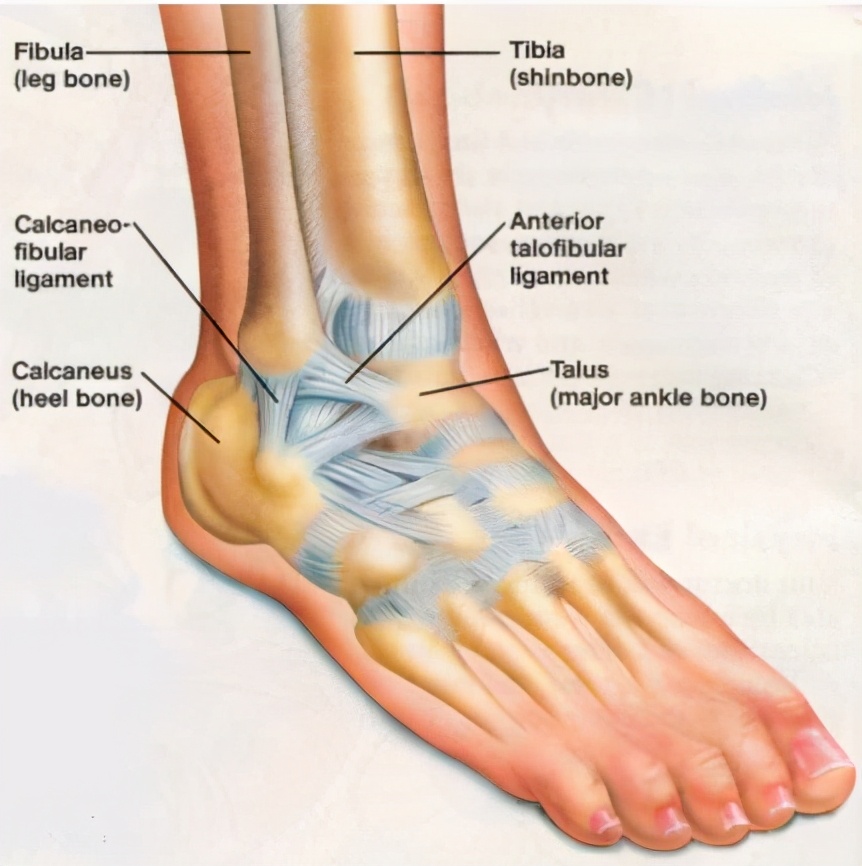

人类的足是个既强健又复杂的支撑结构,由28块骨骼构成,骨与骨之间构成33个关节(其中20个有活动能力)。足部的骨骼构成足弓,像一个吊桥将足撑起来,起到类似弹簧的作用。有超过100条以上的肌肉、肌腱、韧带来维持这个吊桥样足弓的稳定和弹性。(这比科幻片《终结者2》一开头那个踩碎人类头颅骨的机器人战士僵硬的金属大脚复杂多了。)

扁平足可能源于胫后肌力量较弱或有陈旧损伤。胫后肌起自小腿经内踝止于足部,像拉起吊桥的悬索。位于足底的足内在肌力量也不足,不能给脚足够的拉力,韧带也松弛无力,使足变得又软又宽又扁,坐着时脚还显得挺顺溜,一站起来就成大脚板了。扁平足的人在行走时内侧足弓陷落,足过度内旋,足底筋膜受牵连,足底的肌肉受挤压,如果长时间站立行走会感到足底和小腿疼痛乏力。

有扁平足的人在行走时由于足过度内旋会引发一系列包括踝关节、膝关节、髋关节及脊柱的连锁反应,引起小腿、臀部及腰背不适或疼痛。鞋底内侧磨损严重导致失衡更容易引起踝关节损伤和肌腱劳损。扁平足还容易引起拇外翻和拇囊炎。